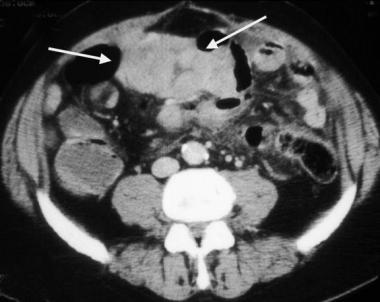

Gambar Usg Tumor Rahim

Tumor Kandungan Mioma Kista | pengobatan penyakit tumor | gangguan kesuburan Obat Herbal Kanker Rahim dan Serviks Hamil anggur - gejala, penyebab, dan cara menanganinya | theAsianparent Indonesia KESEHATAN PASIEN: January 2013 Dr.prima - dokter spesialis kandungan - “Tumor Mioma saat hamil” Tumor pada otot dinding rahim dikenal juga sebagai Mioma/fibroid. Asalnya dari otot rahim bentuknya benjolan daging mirip bakso. Beda dengan kista, benjolannya BILIK SONOGRAFER : Kista Ovarium Cara Membaca Foto USG: 8 Langkah (dengan Gambar) - wikiHow MACAM-MACAM KISTA. Dari USG bisa… - dr Yudhistya SpOG | Facebook Pertama di Dunia, Dokter Berhasil Angkat Tumor Janin dalam Rahim Gisantia Bestari — Hamil Dengan Rahim Spesial Alasan Perempuan Perlu USG Sekali Setahun KB Spiral Wanita Ini Menembus Dinding Rahim Hingga Kandung Kemih, Jarang Terjadi Tapi Risikonya Fatal! - Semua Halaman - Grid Health 5 Langkah Membaca Hasil USG yang Bisa Bunda Pelajari Kista di Rahim | Sehat PLUS Cantik Kista 5 Kg Ibu Hamil Hilang Tanpa Operasi Halaman all - Kompasiana.com Terjadi Lagi, Bayi Baru Lahir Ini ‘Mengandung’ Janin Kembarannya Sendiri Sejak dalam Kandungan - Semua Halaman - Grid Health Kanker Payudara: Setelah Kemoterapi dan Radioterapi Kanker Menyebar ke Hati Nya – Mengenal Kanker Dokter Chandra: Rahim Membesar Belum Tentu Hamil, Bisa Jadi Tumor - Padang Media Apa Sebab Rahim dan Indung Telur Tak Berkembang? | Kaltim Post Ingin Terhindar dari Kista? Jauhi 4 Jenis Makanan Enak Ini Sekarang! - Semua Halaman - Grid Health MACAM-MACAM KISTA. Dari USG bisa… - dr Yudhistya SpOG | Facebook Tadinya Diperkirakan Tumor Rahim yang Lengket Usus, Taunya ‘GIST’ - Kompasiana.com Tumor Kandungan (Miom, Kista) – ask-dr. David Mayndra Utama, SpOG Mengenal Kehamilan Kosong atau Blighted Ovum (BO) - Bidanku.com Harus Operasi Rahim Karena Infeksi Suntik KB, Kisah Wanita Ini Pilu - Lifestyle Fimela.com Kesha Ratuliu Ungkap Hasil USG Payudara, Jangan Tertukar, Ini Beda Tumor dan Kista - Halaman all - TribunStyle.com wanita wajib tahu, inilah rahim sehat - YouTube Bagaimana Cara Membaca Hasil USG? • Hello Sehat Dokter Spesialis Kebidanan Dan Penyakit Kandungan T-end RI: Teknik Pemeriksaan USG Vesica Urinaria dan Uterus Tumor Kandungan Mioma Kista | pengobatan penyakit tumor | gangguan kesuburan Kenali Cara Membaca Hasil USG Untuk Tahu Kondisi Bayi - Ibupedia Bila Terpaksa Hanya Menyisakan Leher Rahim Si Nona Halaman all - Kompasiana.com Wanita Lajang Perlu Waspadai Penyakit Kanker Ovarium USG Payudara: Fungsi, Prosedur, dan Persiapan yang Diperlukan Hal-hal yang Dapat Menjadi Faktor Penyebab Posisi Janin Jadi Sungsang Penyebab janin dalam kandungan menghilang Selain Kehamilan, Tes USG Bisa Deteksi 5 Kondisi Ini MACAM-MACAM KISTA. Dari USG bisa… - dr Yudhistya SpOG | Facebook Ahli Kista: September 2013 5 Tanda Kamu Mungkin Terkena Kanker Rahim - Alodokter Mengenal Istilah pada Hasil USG Kehamilan di Trimester Pertama Infertilitas atau susah punya anak – FeryWijayaSpOG operasiginekologi Instagram posts (photos and videos) - Picuki.com Kenali Perbedaan Tes USG Abdominal dan Transvaginal Tadinya Diperkirakan Tumor Rahim yang Lengket Usus, Taunya ‘GIST’ - Kompasiana.com Macam-macam USG untuk Pemeriksaan Kandungan | OTC Digest USG Transvaginal dan Perut, Mana yang Lebih Baik? Diagnosis Sindrom Ovarium Polikistik - Alomedika Tendangan Keras Bayi di Dalam Perut Bikin Rahim Sang Ibu Robek hingga Kaki Bayi Keluar - Halaman all - Tribun Medan Dikira Cuma Masuk Angin, Dokter Ini Tercengang Saat Temukan Kista Sebesar Bola Sepak di Dalam Perut Pasiennya! - Semua Halaman - Grid.ID Tumor jinak & mioma uteri Kesha Ratuliu temukan benjolan tumor di payudaranya, kenali gejalanya! | theAsianparent Indonesia Welcome to FITRULLAH DOT COM ******* Daily Note: Global Society Care and Research ! ****: Hasil Tes USG Penderita Tumor Payudara: Tumor Lenyap! Kehamilan Membuat Saya Terkena Kanker Serviks’ Operasi Pengangkatan MIOM Tanpa ANGKAT Rahim(dr Boy Abidin) - YouTube Kirain Turun Berok, Ternyata Hamil dan Akhirnya Keguguran (bagian 2) Hasil USG Tunjukkan Ada Gelembung dalam Rahim,Faktanya Bikin Wanita Menangis,Ternyata Janinnya - Tribun Sumsel Kumpulan Artikel Tumor Payudara Inilah Perbedaan antara USG 2D dan USG 3D Unggah Foto USG, Kesha Ratuliu Dikira Hamil Padahal Belum Nikah. Ternyata itu Bukan Foto Rahim Cara Membaca Foto USG: 8 Langkah (dengan Gambar) - wikiHow Pyometra, Penyakit Infeksi Rahim Pada Anjing - Kesehatan Anjing - AnjingKita.Com 5 Fakta Kista Coklat yang Harus Diketahui | Popmama.com Gejala Kanker Serviks, Penyebab, Biaya Berobat & Dokter - Smarter Health Miom - Gejala, penyebab dan mengobati - Alodokter Pemeriksaan USG Transvaginal vs USG Abdominal: Lebih Baik Mana? Muncul Tanpa Gejala, Ini 5 Cara Diagnosis Fibroid Rahim BAB II TINJAUAN PUSTAKA. Tumor ovarium adalah neoplasma yang berasal dari jaringan ovarium. Tumor ovarium - PDF Download Gratis Pengalaman ; Kista, Laparoskopi – Bayi Tabung – IVF | : : ZABANIYYAH : : Bagaimana Membedakan Tumor Jinak dan Ganas - Futuready Keguguran Bisa Dideteksi Dari Setiap Tahap Kehamilan – Apakabar Online Tumor jinak & mioma uteri 10 Ciri-Ciri dan Gejala Miom Rahim yang Mudah Dikenali | HonestDocs Kondisi Begini Membuat Wanita Harus Melakukan USG Transvaginal Manfaat USG Tidak Hanya Untuk Penentuan Jenis Kelamin Janin | Medicalogy MACAM-MACAM KISTA. Dari USG bisa… - dr Yudhistya SpOG | Facebook gambar pemeriksaan usg by aa craft USG Transvaginal, Pemeriksaan yang Ampuh Deteksi Penyakit di Area Panggul, Cek yuk! - Semua Halaman - Grid.ID Jual Manjur obat kanker leher rahim kista tumor kanker payudara rekomendasi - Kab. Cilacap - Toko Pengobatan Herbal. | Tokopedia Unggah Foto USG, Kesha Ratuliu Dikira Hamil Padahal Belum Nikah. Ternyata itu Bukan Foto Rahim Kista Fungsional, Bahaya Nggak Sih ? – esshintaku Tanda Janin Sedang Bermasalah dalam Rahim per-Trimester - Mommies Daily Diagnosis Penyakit Radang Panggul (PID) - Alomedika Genbest - Generasi Bersih dan Sehat 3 Cara Membaca Hasil USG yang Benar, Biar Nggak Salah Kaprah | merdeka.com Mioma Uteri | Gejala, Diagnosis, Pengobatan Apa saja kondisi rahim bermasalah yang perlu diwaspadai? Cara Membaca Foto USG: 8 Langkah (dengan Gambar) - wikiHow BAB II TINJAUAN PUSTAKA. Tumor ovarium adalah neoplasma yang berasal dari jaringan ovarium. Tumor ovarium - PDF Download Gratis Pakai USG, Janin Ini Menendang Keras Rahim Ibunya Hingga Kakinya Keluar, Dokter pun Panik - Tribun Pekanbaru Jual Produk Kista Rahim Herbal Murah dan Terlengkap Maret 2020 | Bukalapak Benjolan di Perut, Ini 7 Gejala Tumor Jinak Rahim 6 Potret Kondisi Suteng Pengasuh Arsy Hermansyah Pasca Operasi 10 Jam, Lemas Tak Berdaya - Kapanlagi.com Kenali Perbedaan Miom dan Kista - Investor.ID PEMERIKSAAN ULTRASONOGRAFI (USG) MUSKULOSKELETAL M BIOPRO ASLI Obat Herbal Miom Tanpa Operasi - Obat Ampuh Kista Ovarium - Kista Dermoid - Kanker Serviks - Kanker Rahim - Kanker Payudara - Tumor - Kanker Uterus Abnormal - BAB 2 TINJAUAN PUSTAKA Ciri-Ciri Rahim yang Sehat dan Subur, Wajib Diketahui Wanita USG, Ini yang Harus Anda Ketahui - Alodokter